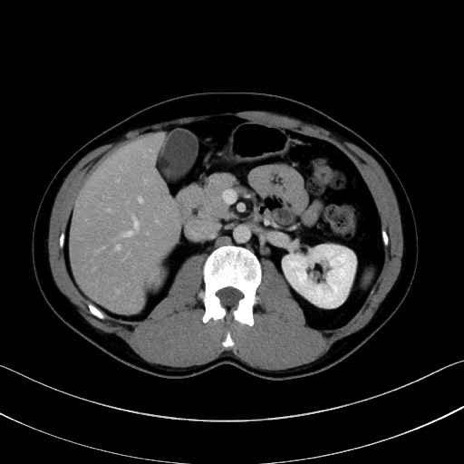

【症例】20歳代 男性 スクリーニング

■起始:典型的には腹腔動脈幹(celiac trunk)から左胃動脈・総肝動脈とともに三分岐し、脾動脈は左後上方へ向かう。

■走行:膵上縁または膵実質背側を蛇行しながら左方へ進み、膵尾部近傍で脾門へ至る。蛇行の程度は個体差が大きい。

■終枝:脾門部で複数の終末枝に分かれ、上極・下極枝や脾門枝群を形成する。胃短動脈群や左胃大網動脈はしばしば脾動脈から分岐する。